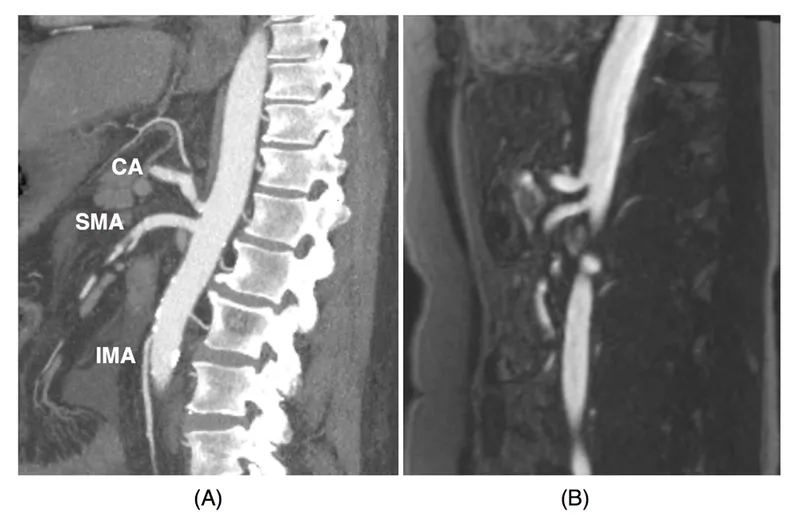

- Primary Arteries:

- Celiac Trunk: Supplies foregut (e.g., stomach, duodenum).

- Superior Mesenteric Artery (SMA): Supplies midgut (e.g., jejunum, ileum, right colon).

- Inferior Mesenteric Artery (IMA): Supplies hindgut (e.g., left colon, rectum).

- Duplex ultrasound (screening).

- CTA or MRA (confirmatory, preferred).

- Conventional angiography (gold standard, allows intervention).